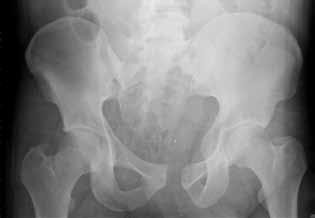

Figure 7Figure 7 is the pelvic radiograph of a 33-year-old man involved in a high-speed automobile crash. Examination reveals a blood pressure of 90/50 mm Hg and a pulse rate of 120/min. Radiographs of the chest and lateral cervical spine are normal. A CT scan of the abdomen does not reveal any intraabdominal bleeding. What is the most appropriate management for the pelvic fracture?